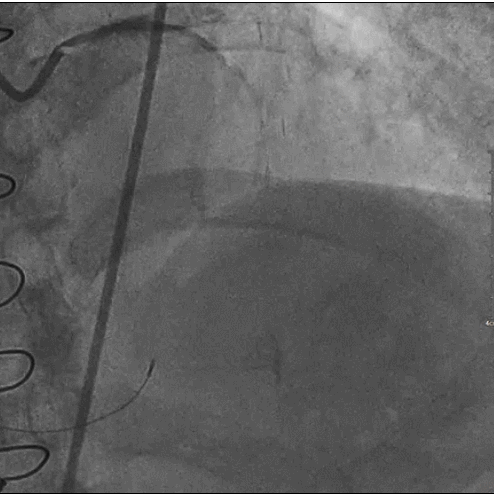

造影: